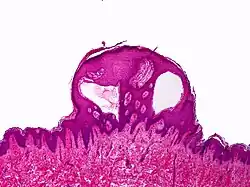

| Lymphangioma circumscriptum; only stratum papillare is affected. | |

A biopsy of the affected skin and histological examination under a microscope are necessary to confirm the diagnosis of lymphangioma circumscriptum.